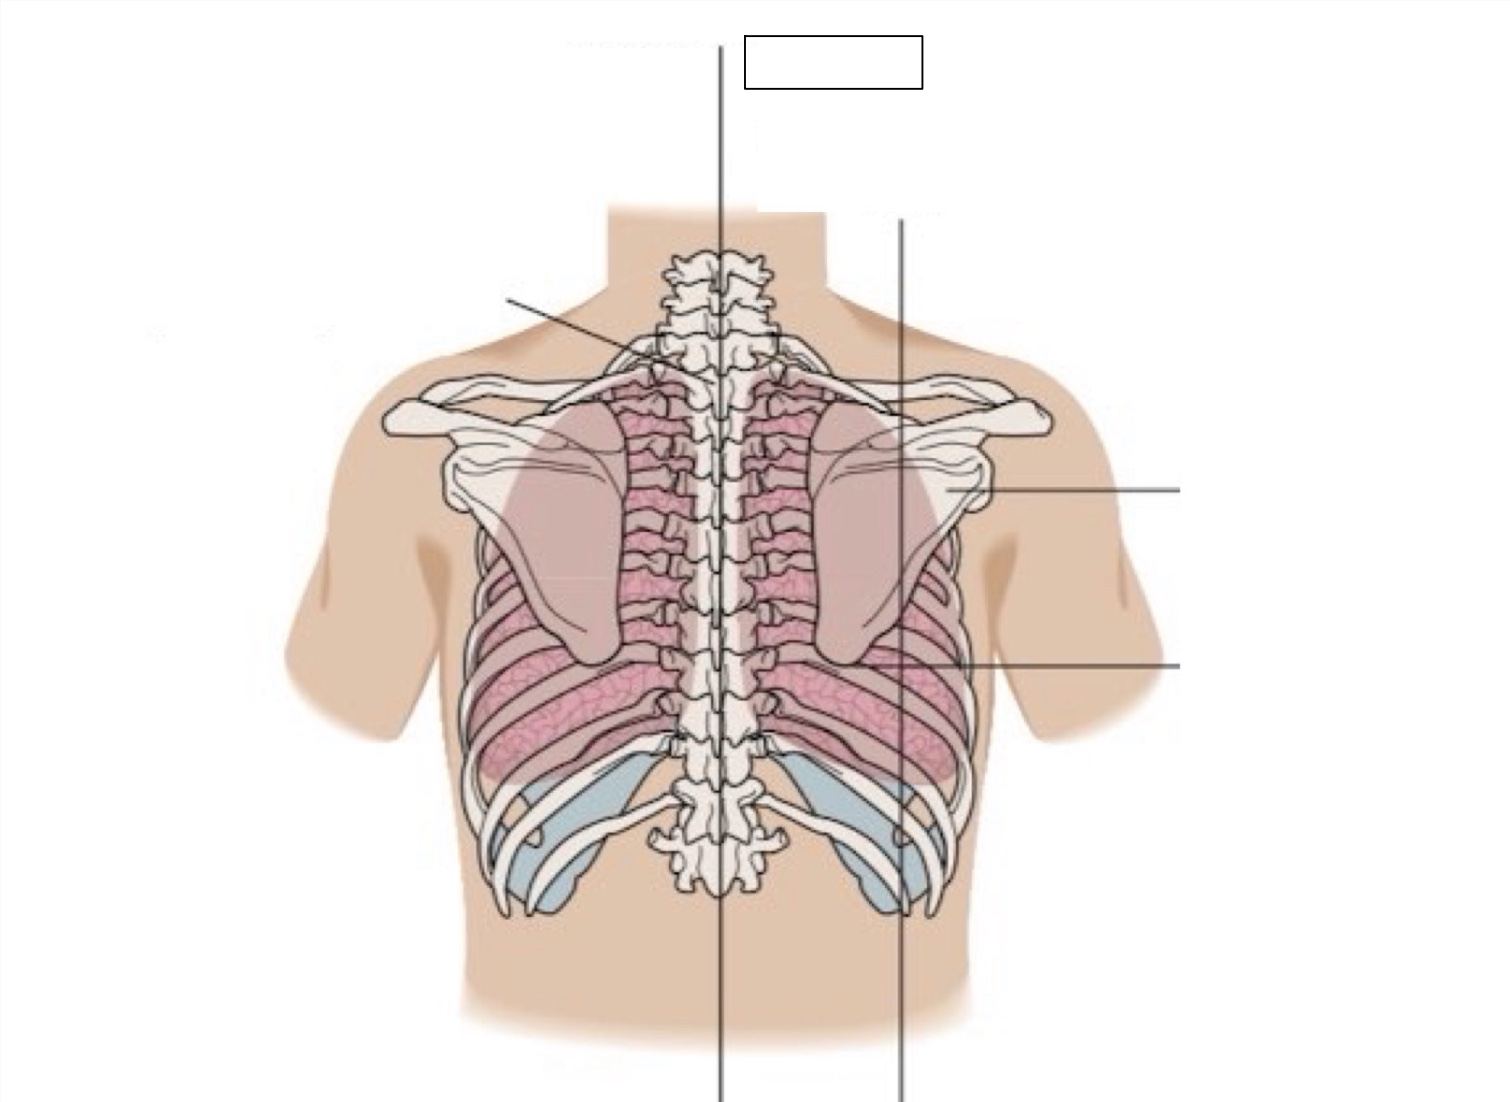

inferior angle of scapula

scapula

midscapular line

midspinal line

spinous process

thoracic cavity

diaphragm